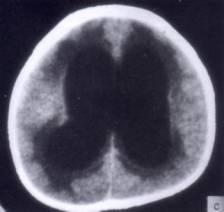

病历摘要:??患者女性,10岁。结核性脑膜炎愈后8月,头痛伴恶心呕吐1周,并渐加重。体检:神清,精神差,反应迟钝,双眼底视神经乳头水肿,双眼外展差,余未见...

问题 病历摘要:??患者女性,10岁。结核性脑膜炎愈后8月,头痛伴恶心呕吐1周,并渐加重。体检:神清,精神差,反应迟钝,双眼底视神经乳头水肿,双眼外展差,余未见明显异常。 下列关于颅内压增高的叙述哪些是正确的?